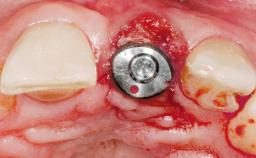

Immediate Placement of an Implant in a Maxillary Right Central Incisor Site

A 30-year-old female patient was referred to the office for the treatment of tooth 11. Her chief concern at the initial visit was to inquire, “Why is my tooth pink?” Upon clinical examination, it was determined that tooth 11 had a previous history of trauma and that the clinical crown had become noticeably pink in color as a result of internal resorption. This diagnosis was confirmed radiographically, indicating a large radiolucency involving the central and distal portions of the clinical crown. It was determined that restoration of this tooth was not possible, and that extraction was indicated. The presence of a mid-line diastema, which the patient wanted to reproduce, directed the treatment plan for tooth replacement utilizing a dental implant.

Placement Protocol Immediate implant placement

Tooth Site Maxillary incisor or canine

Socket Morphology Single-root socket

Socket Integrity Sufficient, with intact bone walls

Bone Volume Sufficient, with intact walls